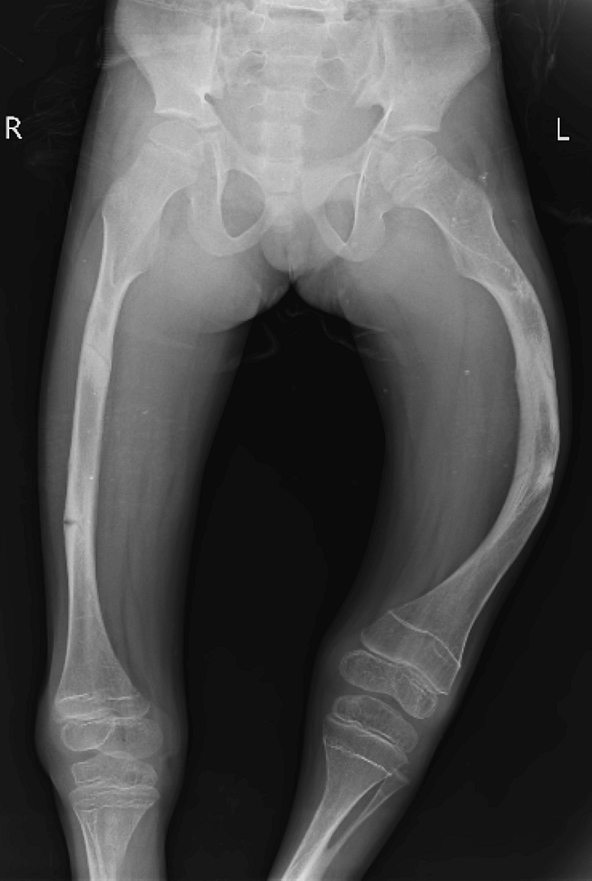

اختلال استخوانزایی نوع 3 یا OI نوع 3، یک شکل شدید از این بیماری است که باعث شکستگیهای مکرر استخوانها میشود. در این نوع، بدن کودک کلاژن کافی تولید میکند اما کیفیت آن مناسب نیست. استخوانها ممکن است حتی قبل از تولد شروع به شکستن کنند و ناهنجاریهای استخوانی با بزرگتر شدن کودک بدتر میشود.

اختلال استخوانزایی نوع 4 یا OI نوع 4، متغیرترین شکل استئوژنز ایمپرفکتا است که علائم آن میتواند از خفیف تا شدید متفاوت باشد. مانند OI نوع 3، در این نوع نیز بدن کلاژن کافی تولید میکند اما کیفیت آن ضعیف است. کودکان مبتلا به OI نوع 4 معمولاً با پاهای خمیده متولد میشوند، اگرچه این خمیدگی با افزایش سن کاهش مییابد.